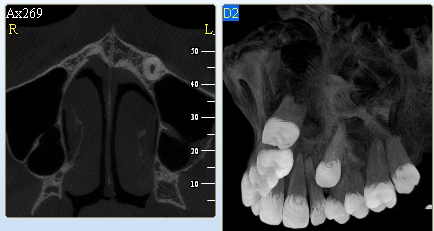

3D DVT - NewTom

Je speciální zubní digitální tříprostorový tomograf (3D), který umožňuje na základě jediného

snímkování vytvořit všechny typy RTG zobrazení, které jsou pro lékaře potřebné. Díky používané technologii tzv. „kuželového paprsku“ a speciálním senzorům je

výrazně zmenšená dávka záření - o více jak 80% proti klasickému CT vyšetření. To je významné zejména u dětí. Pomocí tohoto přístroje je možné zjisti skutečnou situaci v čelistních kostech pacienta tedy množství kosti - můžeme změřit skutečnou šířku i výšku kosti, i kvalitu kosti (hustotu) v místě uvažované implantace. 3D (tříprostorové) zobrazení umožňuje zvýšit prostorovou představu operatéra ještě před vlastní operací a zároveň pacientovi lépe objasnit a ukázat oblast plánovaného zavedení implantátu.

Pacient „neumí číst“ RTG snímky, ale díky 3D zobrazení vidí „svoji skutečnou čelist“

- např. jak je nízká či úzká, vidí průběh nervu nebo velikost čelistní dutiny, což mu umožní i pochopení nutnosti v některých případech provést pomocné zákroky ještě před vlastním zavedením implantátu (viz. kostní štěp, sinus lift, kostní granulát...).

Vyšetření pomocí tohoto přístroje používáme i ve stomatochirurgii (zlomeniny čelistí, zuby moudrosti, cysty, onemocnění čelistního kloubu), ortodoncii (retinované zuby, nadpočetné zuby), parodontologii atd.